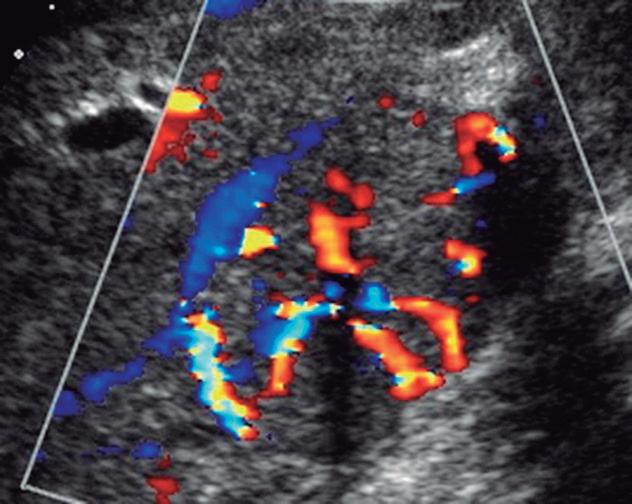

Fig. 2-31. Doppler tipo “roda de carroça” da hiperplasia nodular focal.